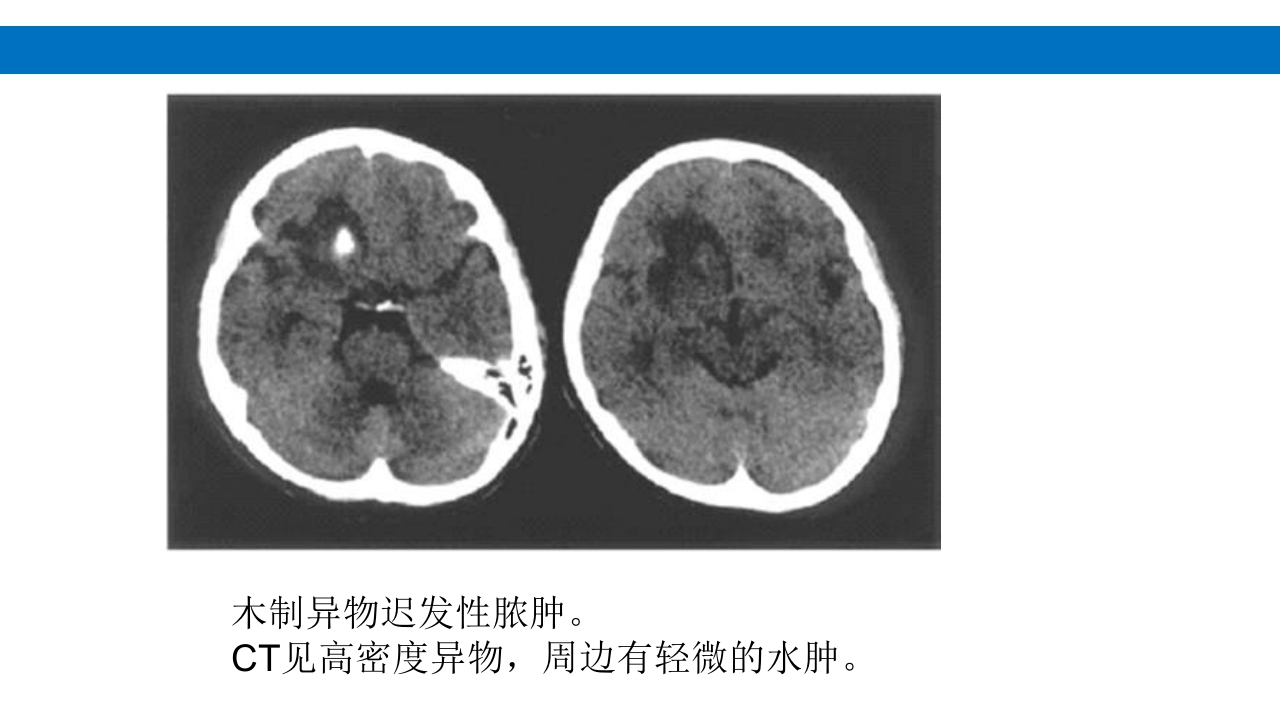

颅脑损伤的并发症及后遗症 讲解人:xxx 20XX年x月x日 1.颅骨骨髓炎 病因:为头皮软组织、中耳、乳突和副鼻窦等处炎性感染而经导 血管侵入颅骨内或颅脑开放伤感染所引起,亦可由菌血症后发生 的细菌栓子由血运转移至颅骨内。 影像学表现: 头部CT: 1.表现为不规则的蜂窝状骨质破坏区,主要位于板障,亦可累 及内外板。 2.破坏区内可见高密度的米粒状细小的高密度死骨。 3.周边可见骨质硬化增生,颅板外无骨膜反应。 4.局部的头皮可见软组织肿胀。 头部MRI: 由于受累部位细胞成分和水量增多,T1WI为低信号, T2WI为高信号,急性期边界不清,慢性期病灶局限, 边界清晰。MRI显示骨质破坏没有CT效果好。 治疗: 除应用抗菌药物控制感染外,当感染局限或已有死骨形成后, 应行手术切除感染...